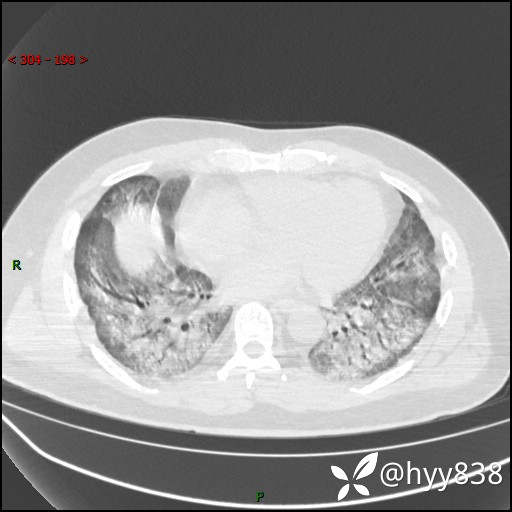

第二次CT(7天后)